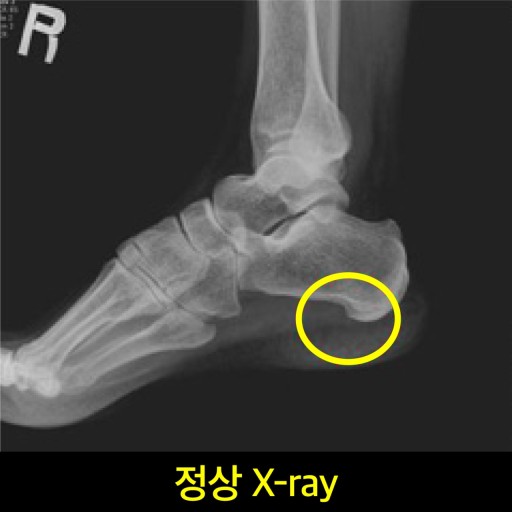

족저 근막염 증상 이런 증상은 **‘족저근막염’**의 대표적인 신호일 수 있어요.

족저근막염은 발바닥을 지지해주는 근막에 염증이 생긴 상태로,